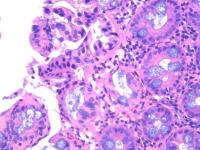

横结肠息肉

性别年龄56临床诊断

一般病史体检

标本名称横结肠息肉

大体所见灰白2粒

肠粘膜息肉。

小灶区域腺上皮有异型,重切一张再看看。

表面黏膜上皮有很少异型细胞。间质中一团上皮样细胞性质不明,没有明显异型性。可描述发报告。